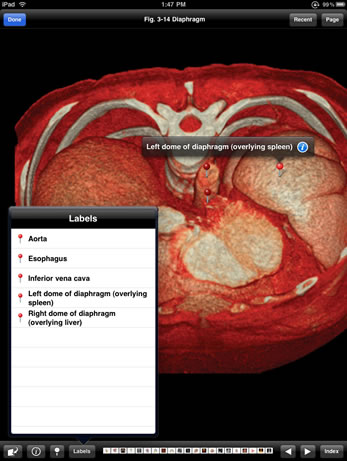

Match modern diagnostic images with a subset of the anatomic drawings from the Atlas of Human Anatomy, by Dr. Frank Netter, and enable a comfortable familiarity with how human anatomy is typically viewed in clinical practice.